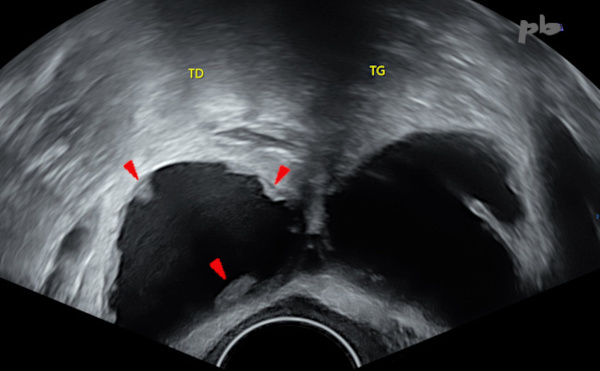

1 – Hydrosalpinx

Echographie endovaginale.

Hydrosalpinx typique : image tubulée, sinueuse, à contenu liquidien.

Absence de flux en mode B (pour les flux très lents) ou en doppler.

1 – Hydrosalpinx

Transvaginal ultrasound. Typical hydrosalpinx: a tubular, serpentine image with fluid content. No flow detected in B-mode (for very slow flows) or on Doppler.